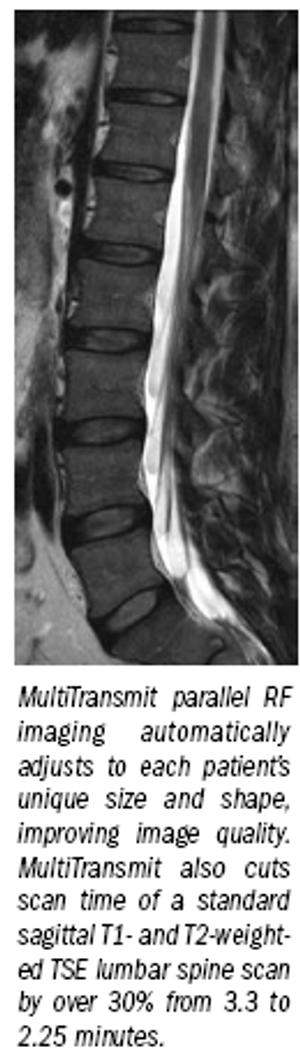

MultiTransmit technology enables customers to realize 3T benefits in breast, body imaging.